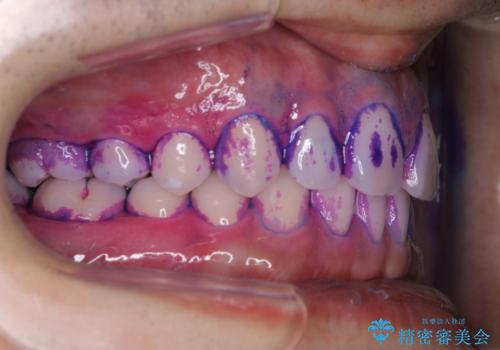

親知らずを抜いて1週間後にPMTC 歯のクリーニング

- 親知らずの抜歯後の約1週間後に抜糸(縫った部分の糸とり)で来院されました。その際、抜歯後は傷口が怖くて歯磨きが上手くできず、汚れや口臭が気になるためクリーニングも希望されました。

抜歯後は多少出血したり、違和感や痛みを感じたりすることがあります。そのため親知らずを抜いたり、外科的な処置をするといつも通りの歯磨きがしづらくなります。また、傷口の周りが心配で、歯ブラシをするのが怖くなるものです。抜歯後落ち着いたら、歯科医院にて専門の機械を使用しクリーニングをすることがおすすめです。抜歯前や後にPMTCを行うことで、お口の中の健康維持につながり、その後の感染・腫れ・口臭予防などになります。

親知らず抜歯後正常に治癒が進んでいれば1週間後から可能です。